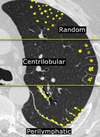

¿Cuáles son los patrones de distribución que pueden tener los nódulos en el patrón nodular?

27

¿Cuál es el acomodo de los nodulos en el patrón miliar?

patrón aleatorio